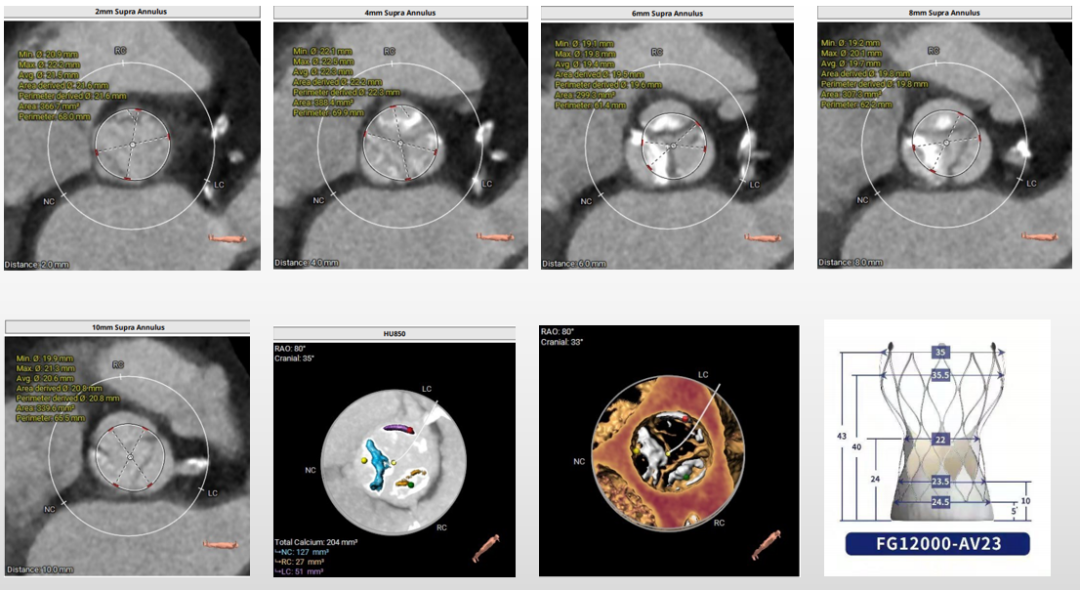

第二例术前评估

主动脉根部评估

三叶式主动脉瓣,瓣叶增厚,流出道呈直筒状,由于瓦氏窦、STJ内径小,左冠窦瓣叶长度>瓣叶附着缘到冠脉开口的距离,术中有冠脉阻挡风险。

瓣环上解剖结构评估

重度钙化,瓣上4-8mm限制最重,根据瓣环及瓣上情况,选20mm球囊预扩、AV23瓣膜。

外周血管及主动脉弓解剖

双侧髂总动脉轻度扭曲少量钙化,双侧髂外动脉内径细,左侧内径稍好,最细5.2mm,选择左侧为主入路,右侧为辅入路。